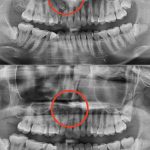

主な理由として、先天欠損歯が挙げられています。先天欠損歯とは、生まれつき永久歯を持っていない『歯の先天性欠如』のことを言います。

今は大きな影響がなくても段々と噛み合わせが合わなくなってきたり、隣の歯が倒れてきて隙間ができ食べカスがつまりやすくなり虫歯が出来てしまうなどのリスクもあるそうです。